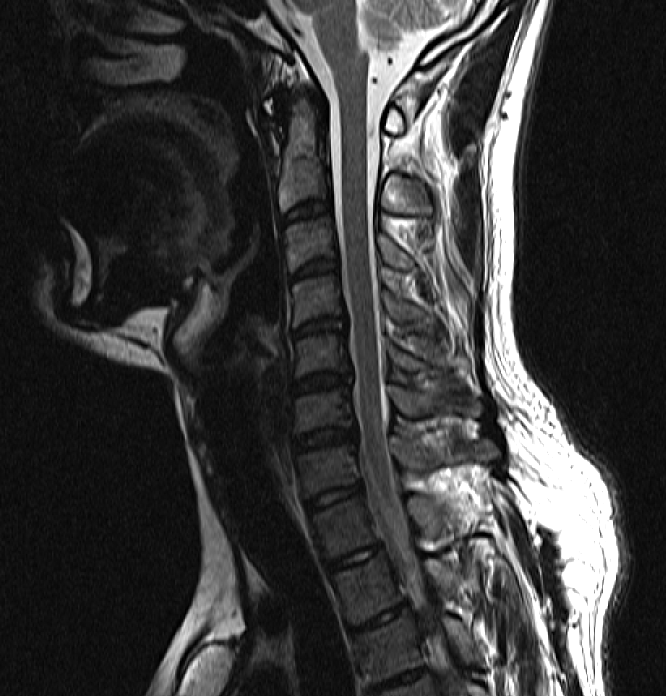

아래는 저의 경추과 요추 MRI 사진 첨부합니다.

• 1번 째 사진

• 2번 째 사진

• 3번 째 사진

• 4번 째 사진

※우리들병원 (신경외과 대표원장) : 경추,요추 MRI 촬영했고 요추는 매우 건강하고 경추에는 일자목에 퇴행성 디스크가 보이지만 한쪽팔에 저림이나 힘빠짐을 유발할 정도는 절대아니고, 다른 원인을 찾아야한다고 했습니다.

※분당서울대병원 재활의학과 : 근전도검사 이상없음, 경추 요추 MRI를 봐도 근골격계 문제로 보기 어렵다. 신경계 문제도 아니다.

3명이 디스크가 아니라고 하는데 1명이 디스크일수 있다고 하니까 조금 어렵습니다. 경추디스크가 약간은 있으니 팔저림은 설명할수 있다해도 다리저림은 설명이 안됩니다.. MRI 결과상 요추는 매우 건강하다고 하셨거든요.